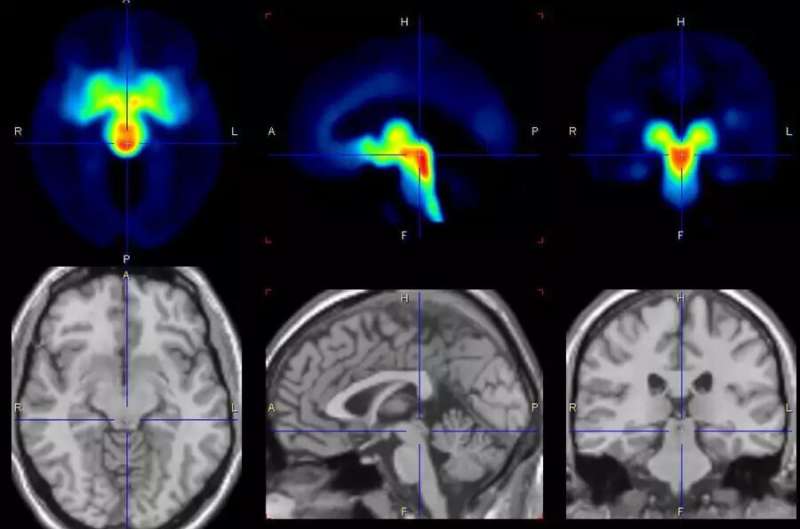

“We examined 30 female patients and 29 healthy study participants over several menstrual cycles and took images of the brain with positron emission tomography (PET) at different cycle times. We found that shortly before menstrual onset, the serotonin-transporter in the brain is increased and thus promotes a synaptic loss of this neurotransmitter, which can explain the affective symptoms in the affected women.

“This finding is surprising because it was previously thought that serotonin transporter density could not change in a short time span of two weeks—normally this is considered to be an individual trait with only minor changes over the period of 10 years is assumed.”